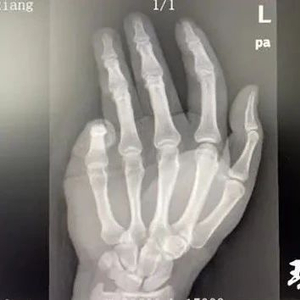

该院手足外科副主任董波接诊后,看到周先生的左手鲜血淋淋,小指远节部分缺失,整个小指皮肤苍白,董波立马将周先生的离体小指用冰块保存好,随即开始帮助周先生清理包扎伤口,并立即为其开通绿色通道,办理入院手续。通过 X 光片检查董波发现,周先生小指末端已经骨折。" 他的小指最后一截已经完全断离,而且指骨骨折,当时的情况,越快手术再植成功率越高。" 董波说道。